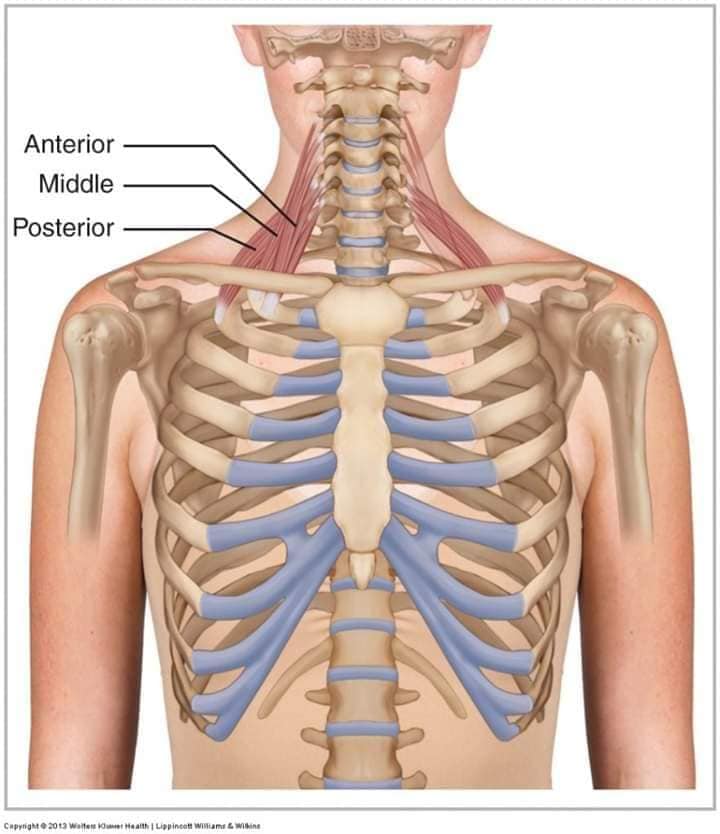

Шийні м'язи

Шийні м'язи мають важливе значення для підтримки голови і забезпечення її рухів.

М'язи задньої групи

М'язи, що розширюють шию: М'язи, що розширюють шию: включають трапецієподібний м'яз, який бере участь у піднятті плечей і розширенні шиї.